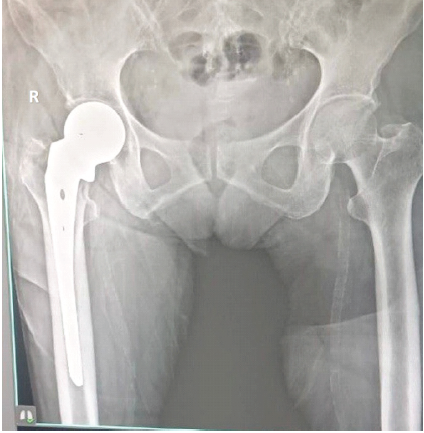

About 10 months postoperatively, she was diagnosed with breast cancer and subsequently began receiving treatment at another hospital. At her most recent evaluation, 25 months after the hemiarthroplasty, her Hip Disability and Osteoarthritis Outcome Score, Joint Replacement (HOOS, JR) score was 80.55. There were no clinical concerns, and radiographs showed no evidence of prosthetic loosening or subsidence (Fig. 4). Unfortunately, she succumbed to breast cancer 1 month later. Throughout the 25-month follow-up period, no clinical or radiological complications related to the hemiarthroplasty were identified.

Figure 4: Follow-up radiograph at 25 months.